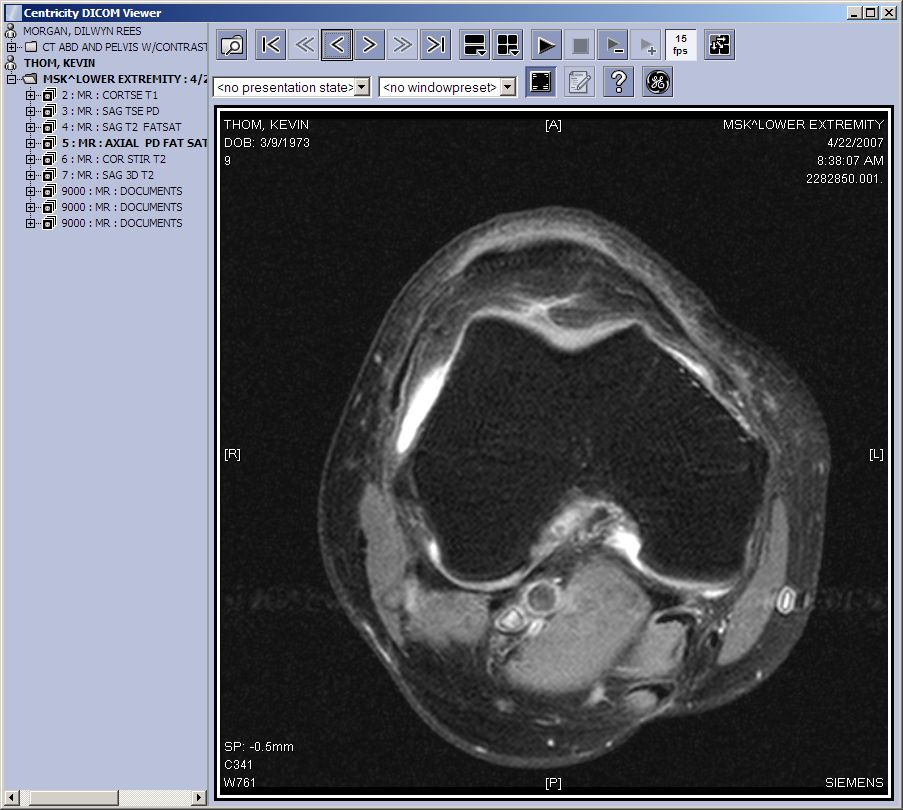

Here’s another scan. This one is a cross section. I think it’s cool to see those veins and bones and muscles. It reminds me of osso bucco (Italian braised veal shank recipe). Yum.